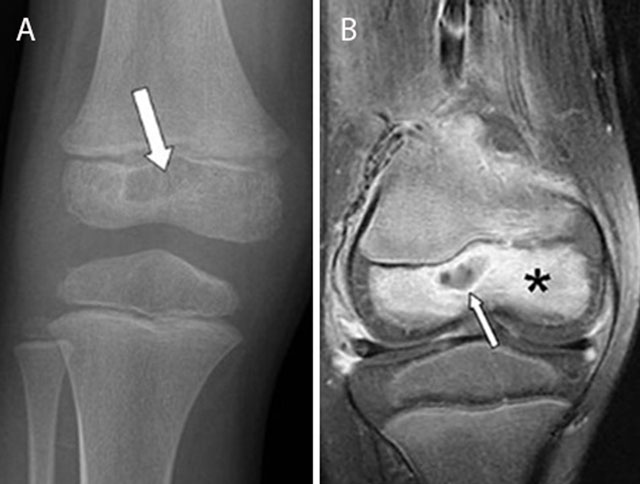

Figure 4

Epiphyseal childhood osteomyelitis of the right knee. Plain radiograph (a) of the distal femur shows a radiolucent lesion with peripheral sclerotic rim (white arrow) in the epiphysis of the distal femur. After gadolinium contrast administration (coronal T1–Fat–Sat WI, (b) the central part of the lesion is non-enhancing whereas there is subtle peripheral rim enhancement (white arrow) with moderate enhancement of the surrounding bone marrow edema.